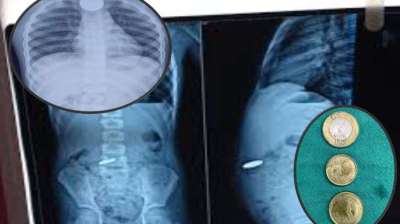

बच्चे ने मुंह में डाले सिक्के, सांस अटकने लगी; मेडिकल टीम की सतर्कता से टली बड़ी अनहोनी

दिल्ली : दिल्ली के एक सरकारी अस्पताल के डॉक्टरों ने 12 वर्षीय बच्चे की जान बचाई है। बच्चे ने पांच और दस रुपये के तीन सिक्के निगल लिए थे। सिक्के...